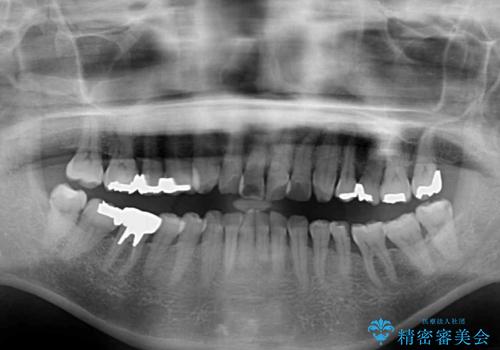

- 口元の突出感と歯の色を気にして来院された患者様です。

口元を引っ込めるために上下左右第一小臼歯4本を抜歯し、ワイヤー矯正を行うこととしました。

歯の色はホワイトニングかセラミッククラウンで対応することとしましたが、ブラックトライアングルが目立つことが予想されたため、目立つ範囲をオールセラミッククラウンで補綴することとしました。